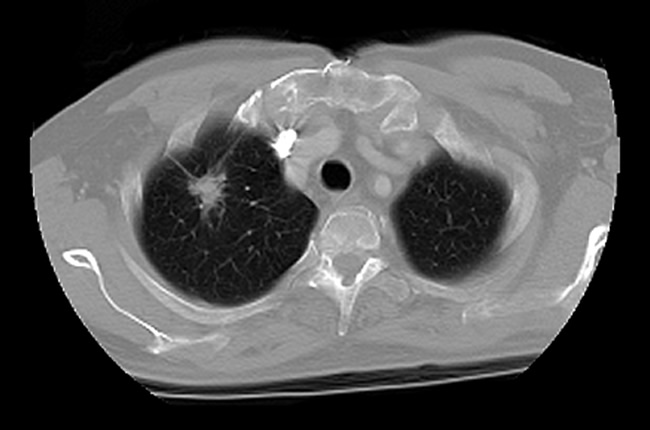

Specific measures of a tumors texture and intensity as they appear on ct images can help determine how much treatment patients with early stage lung cancer need a study found.

Early stage lung cancer ct scan images. It can give more information about any abnormalities nodules or lesions small abnormal areas in the lungs that were. However it is difficult to detect lung cancer in the early stage. The diagnostic methods are ct scans computerized tomography chest radiography x ray mri scan magnetic resonance imaging and biopsies etc.

A chest x ray is usually the first test but it cannot show that the person has cancer. A ct scan takes a cross sectional and a more detailed image of the lung. The surgeon may remove the part of the lung that has the.

Lung cancer does not always produce symptoms in the early stages and this can make it difficult to detect. Diagnosis is based on computed tomography ct images. In this histogram equalization used to preprocessing of the images and feature extraction process and classifier to check the condition of a patient in its early stage whether it is normal or abnormal.